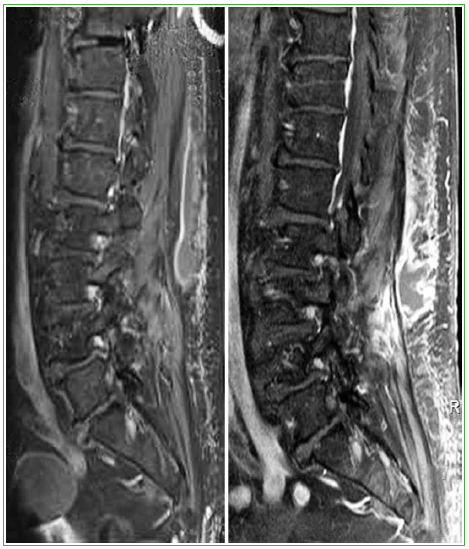

Figura 1.

Resonancia magnética de columna lumbar, corte sagital. Se observa una colección en relación con la musculatura paraespinal derecha, que se extiende de T12 a L4.